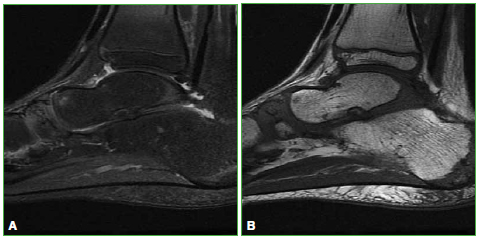

En la resonancia magnética (Figuras 6-8) del pie derecho, puede observarse la fragmentación y el edema óseo en el sector superior del escafoides. También se visualiza una línea negra en secuencias T1 que corresponde a esclerosis ósea.

Figura 6.

Resonancia magnética, plano sagital en secuencias STIR (A) y T1 (B) en el escafoides derecho. Se observa el edema óseo en el sector superior del escafoides tarsiano derecho que se encuentra fragmentado y con leve esclerosis.